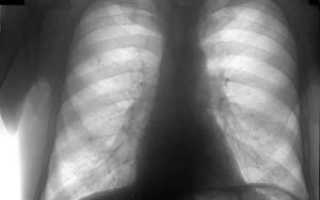

Сердце и бронхи представляются светлыми пятнами. Легочная ткань равномерна, поэтому в норме должна выглядеть на снимке однородной.

Если на флюорограмме видны участки с затемнением, у врача должны возникнуть подозрения на патологический процесс в легких.

Зафиксированные признаки патологии на флюорограмме выглядят следующим образом:

- очаги воспаления в легочной ткани;

- сегментарные уплотнения;

- усиление рисунка сосудов;

- жидкость в плевральной полости;

- расширение и уплотнение «корней» легкого;

- увеличенные лимфоузлы;

- замена части легочной ткани на соединительную.

Чаще всего на изображении будут видны сразу несколько симптомов воспаления. Врачу необходимо их оценивать в комплексе, чтобы понять, каким конкретно заболеванием вызваны патологические изменения в легких.